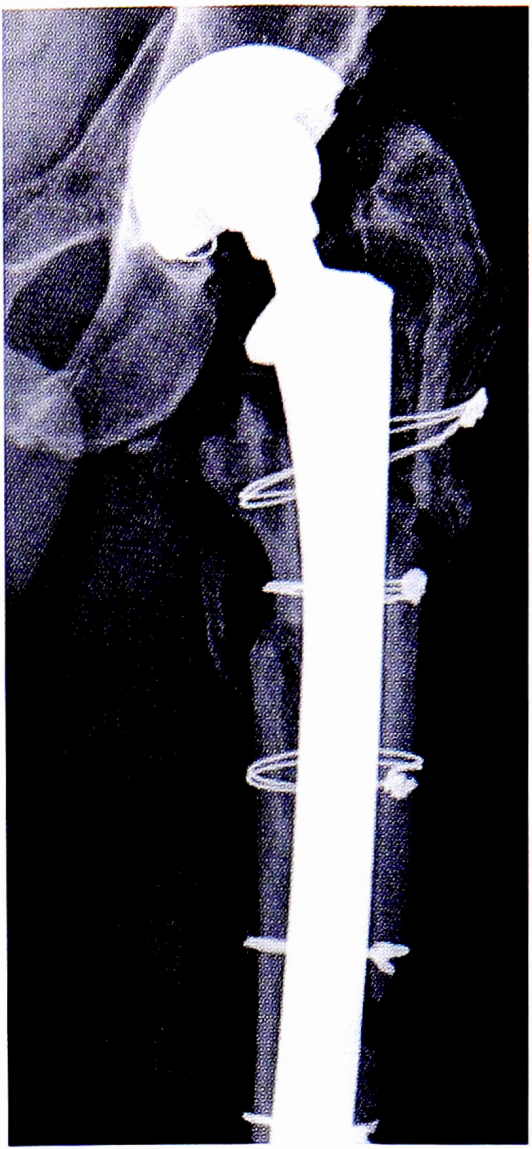

Переломы типа В3 (нестабильные переломы диафиза) чаще всего возникают при вывихивании БК, удалении цемента из канала и имплантации ножки. Для лечения таких переломов также необходимо использовать длинную ножку и кортикальные аллотрансплантаты (если это необходимо) в сочетании с серкляжной проволокой (рис. 6).

Рис. 6. Интраоперационный перипротезный перелом В3. Наложение серкляжной проволоки в сочетании с кортикальным аллотрансплантатом (https://www.or-thobullets.com/recon/5013/tha-periprosthet-ic-fracture).

Fig. 6. Intraoperative periprosthetic fracture B3. Application of cerclage wire in combination with cortical allograft.